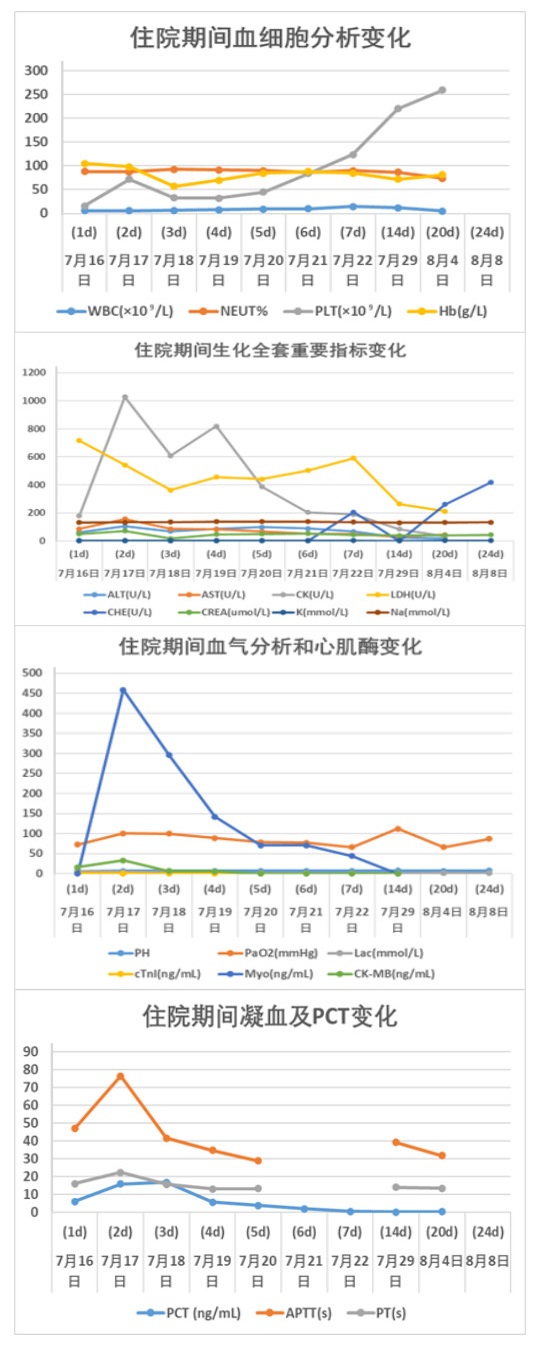

2 结果入院时实验室查急诊血清胆碱酯酶(cholinesterase, ChE):小于196 U/L。血常规:白细胞(white blood cell, WBC)9.24×109/L,中性粒细胞百分比(neutrophil, NEUT%)88.3%,PLT 230×109 /L,红细胞(red blood cell, RBC) 4.08×109/L血红蛋白(hemoglobin, Hb)128 g/L。动脉血气分析:酸碱度(potential of hydrogen, pH)7.247,二氧化碳分压(partial pressure of carbon dioxide, PCO2)30.2 mmHg,氧分压(partial pressure of oxygen, PaO2)93.8 mmHg(呼吸机辅助通气下吸氧浓度为50%),氧合指数284.3%,血钠(Na+) 141.1 mmol/L,血钾(K+) 3.25 mmol/L,乳酸(lactic acid, Lac)8.35 mmol/L,血糖16.05 mmol/L,碳酸氢根12.8 mmol/L,碱剩余-13.2 mmol/L。床旁快速心肌酶:心脏特异性肌钙蛋白Ⅰ(cardiac troponin, cTnⅠ)0.17 ng/mL,肌红蛋白(myoglobin, Myo)123.6 ng/mL,肌酸激酶同工酶(creatine kinase, myocardial-type, CK-MB)17.83 ng/mL。床旁NT-proBNP: 106 ng/L,肝功能:天门冬氨酸氨基转移酶(aspartate aminotransferase, AST)162 U/L,丙氨酸氨基转移酶(alanine aminotransferase, ALT)86 U/L,肌酸激酶196 U/L,乳酸脱氢酶(lactate dehydrogenase, LDH)302 U/L。肾功能:肌酐(creatinine, CREA)104 μmol/L,尿素氮4.84 mmol/L。凝血常规:PT 12.9 s,APTT 34.7 s。新冠病毒抗体阴性。急性感染三项:白介素6 1 148.0 pg/mL,降钙素原(procalcitonin, PCT)0.688 ng/mL,超敏C反应蛋白0.78 mg/L。后期上述指标变化见图 1。床旁胸片显示,(1)双肺纹理增多、增粗、模糊,双肺感染可能;(2)左侧胸腔少量积液可能。见图 2。住院期间讨论CT示:硬膜下积液,见图 3。

| 图 1 患者住院期间主要实验室检查结果 |